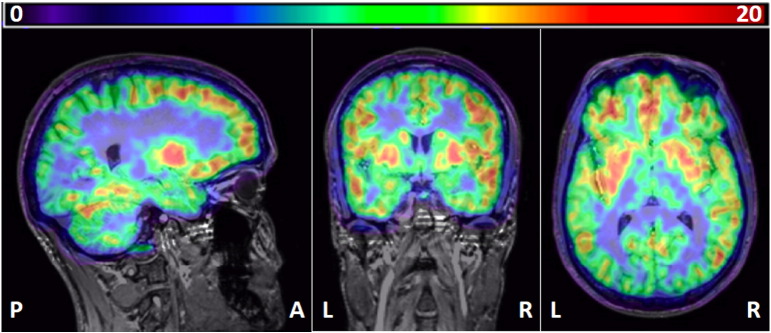

Sampling parametric VT images obtained with “classic” spectral analysis

The region with the highest VT was the pallidum (15.8; Table 5). Regional heterogeneity of VT values was moderate, with a ratio of pallidum over pons of 3.6. ICCs were fairly homogenous between regions and ranged between 0.76 and 0.87, with a mean ± SD of 0.83 ± 0.03. Fig. 4 shows an example of a parametric map.

Table 5: Subjects’ volume of distribution (VT) obtained with “classic” spectral analysis (SA) on parametric maps. ACG = anterior cingulate gyrus, IFG = inferior frontal gyrus, caudate = caudate nucleus, pallidum = globus pallidus, accumbens = nucleus accumbens. BS = between-subjects, CV = coefficient of variation, diff = difference, ICC = intraclass correlation coefficient, Min = minimum, Max = maximum, ROI = region-of-interest, SD = standard deviation.